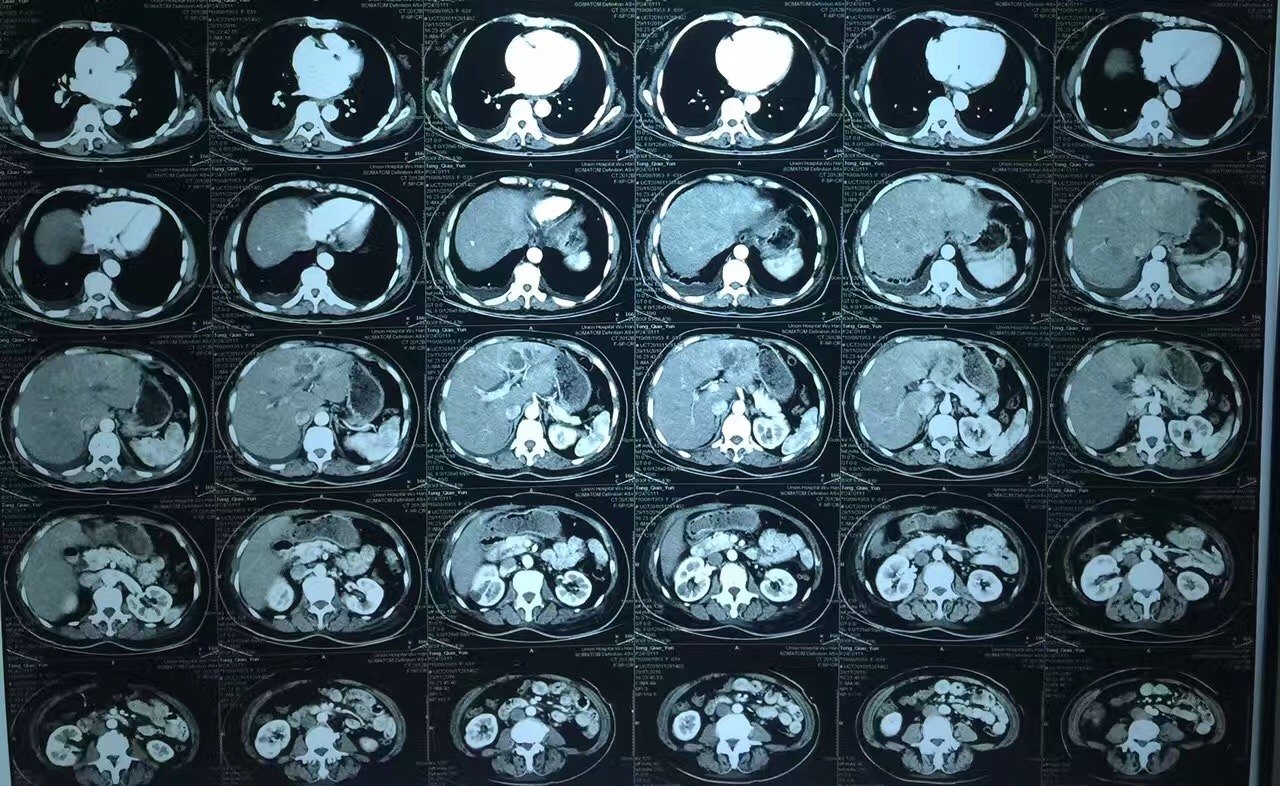

弥漫性脂肪肝伴正常肝岛一例ct增强病例

增强扫描,肝岛表现与脂肪浸润区同步均匀强化.